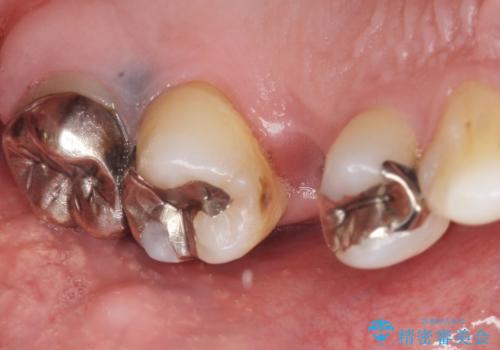

- 奥歯のかぶせ物が土台ごとはずれてしまったことを主訴に来院された患者様です。

残根状態になっている左上の小臼歯(左上5)を精査したところ、う蝕が歯肉縁下まで進行しており保存不可能な状態でした。

患者様のご希望により、抜歯後インプラント治療を行いました。